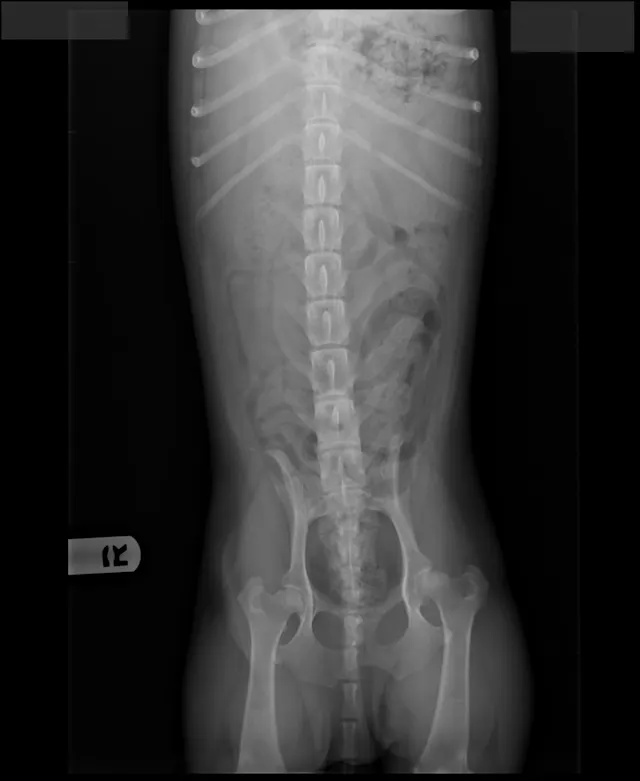

FIGURE 1

Radiographs of Ernest at 8 years of age at a recheck examination